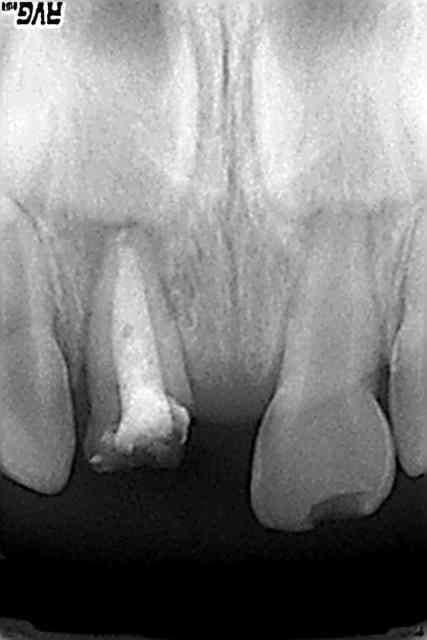

patiente vue en urgence decembre 2009, obturation + reconstitution + prov,revue une semaine après,plus de douleurs,fistule en voie de disparition

en fevrier RAS bien que l'image n'ait pas disparu(en 2 mois c'est impossible)

pose de la ceramique fin fevrier

RAS depuis

attendre oui mais pas non plus trop longtemps(risque de desct prov ou si tu n'en as pas fait,réinfiltration ou fracture,etc... )